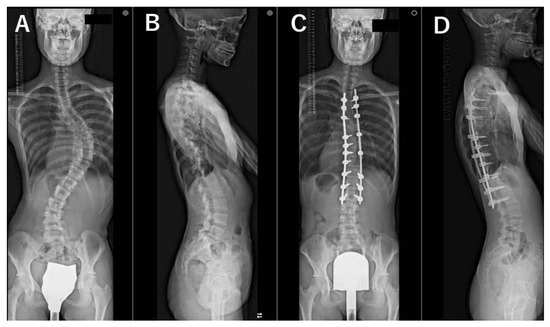

2. Materials and Methods

3. Results

3.3. Radiographic Evaluations